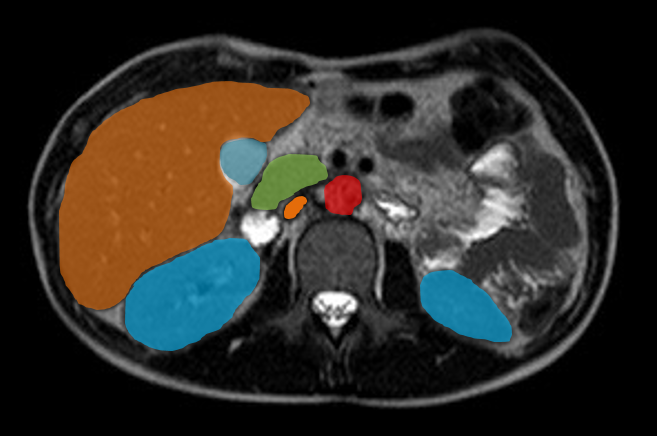

Bildergalerie (5 Bilder)